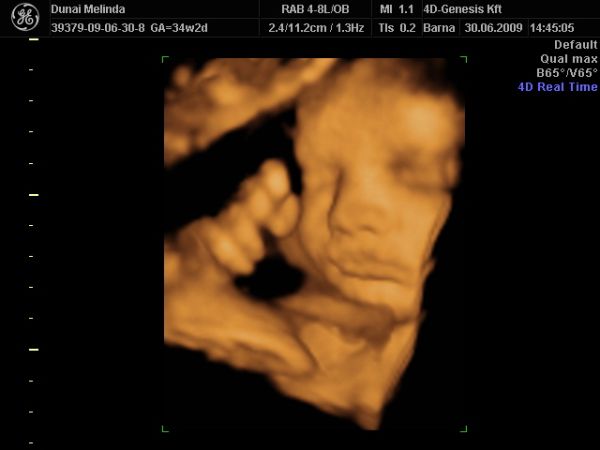

most elvileg megint vagy 10 hétig nem nézik Bogyót, 28-30. héten van megint kötelező UH. Iktass be közte egy 4D-t, ha tudsz. Én továbbra is javaslom a 4D Genesis-t, mi kedden megyünk másodjára. Olyan kedves az a nő, annyi mindent megnéz, nem csak a baba állapotát, hanem a tied is, és tuti nem enged úgy el, hogy ne hozza valahogy össze, hogy megkukkoljátok a lába közét, ha szeretnéd.

KépKép